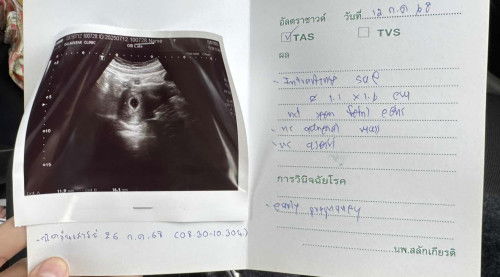

ท้อง6วีค อัลตราซาวแล้วยังไม่เจอน้อง

ท้อง7วีค อัลตร้าซาวด์เจอแต่ถุงไข่ไม่เจอน้องเลย แอบกังวล คุณหมอบอกอีกอีก2ทิตไปใหม่